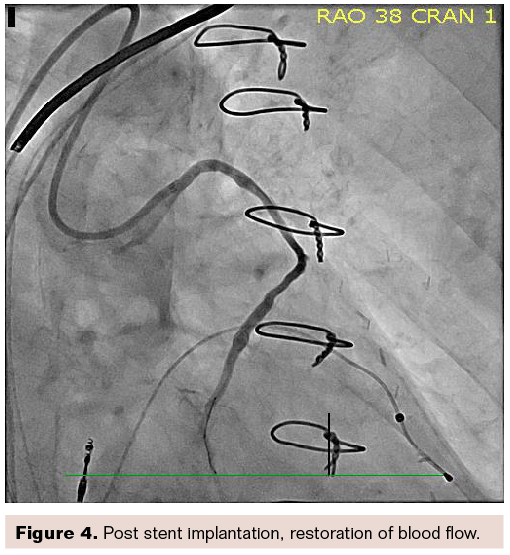

Figure 4 shows a nice final result.